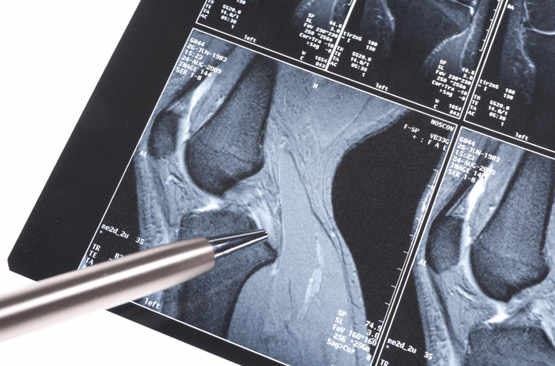

Les ligaments croisés antérieurs du genou à l'épreuve du ski

Fréquemment touchés lors d’accidents de ski, les ligaments croisés antérieurs sont des structures clés...

Douleurs du genou

La déchirure du ménisque ne touche pas que les sportifs

Genou douloureux: ses causes et ses traitements

Avoir mal aux genoux est fréquent. Cette articulation est en effet particulièrement sujette aux traumatismes,...

On peut soigner des ligaments du genou déchirés sans opérer

Un nouveau ligament dans le genou?

Il va peut-être falloir remanier les manuels d’anatomie, en particulier le chapitre sur le genou. Celui-ci...

Le retour au sport après une opération du ligament croisé du genou

Le sportif opéré d’une déchirure du ligament croisé antérieur du genou doit s’armer de patience avant...